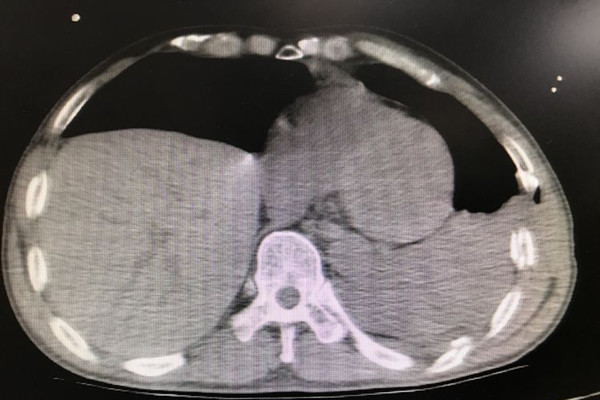

患者李某,在工作时不慎被搅拌机绞压胸腹部及左上肢,急诊转入我院时,颜面部青紫,上半身遍布出血点,左侧胸廓塌陷,反常呼吸明显,右侧呼吸音明显减弱,腹部压痛明显,左上肢严重毁损,情况十分危急。急诊科医护人员立即开通绿色通道,快速完成CT检查,实施紧急救治,并通知胸心外科和麻醉科及辅助科室做好抢救准备。结果提示,患者左侧多根多处肋骨骨折、左侧胸腔积液、右侧膈疝、脾脏破裂,肝脏挫伤,左上肢粉碎性骨折。

患者胸腹部挤压伤并创伤性窒息,病情极其危重,随时都会有生命危险,容不得半点耽搁。在对患者病情与手术方案进行细致的讨论后,由我院胸外科、创伤骨科、普外科、手麻科等科室专家组成的医疗团队立即对患者进行急诊手术抢救。胸外组经胸腔镜辅助行双侧胸腔探查见左侧4-12肋骨骨折,其中4-10肋骨成粉碎性骨折,左肺下叶广泛挫裂伤,胸腔积血2000余毫升,双侧膈肌破裂、肝脏完全疝入右侧胸腔。普外组探查腹腔积血1000余毫升、脾脏破裂。创伤骨科组探查见左上肢粉碎性骨折,软组织毁损严重,在多学科协作下成功完成左侧血胸清除、肺修补、左侧膈肌修补、左侧肋骨骨折复位内固定术等手术。各学科争分夺秒,配合默契,凭借着娴熟的医疗技术和丰富的临床经验,让奄奄一息的患者重获新生。